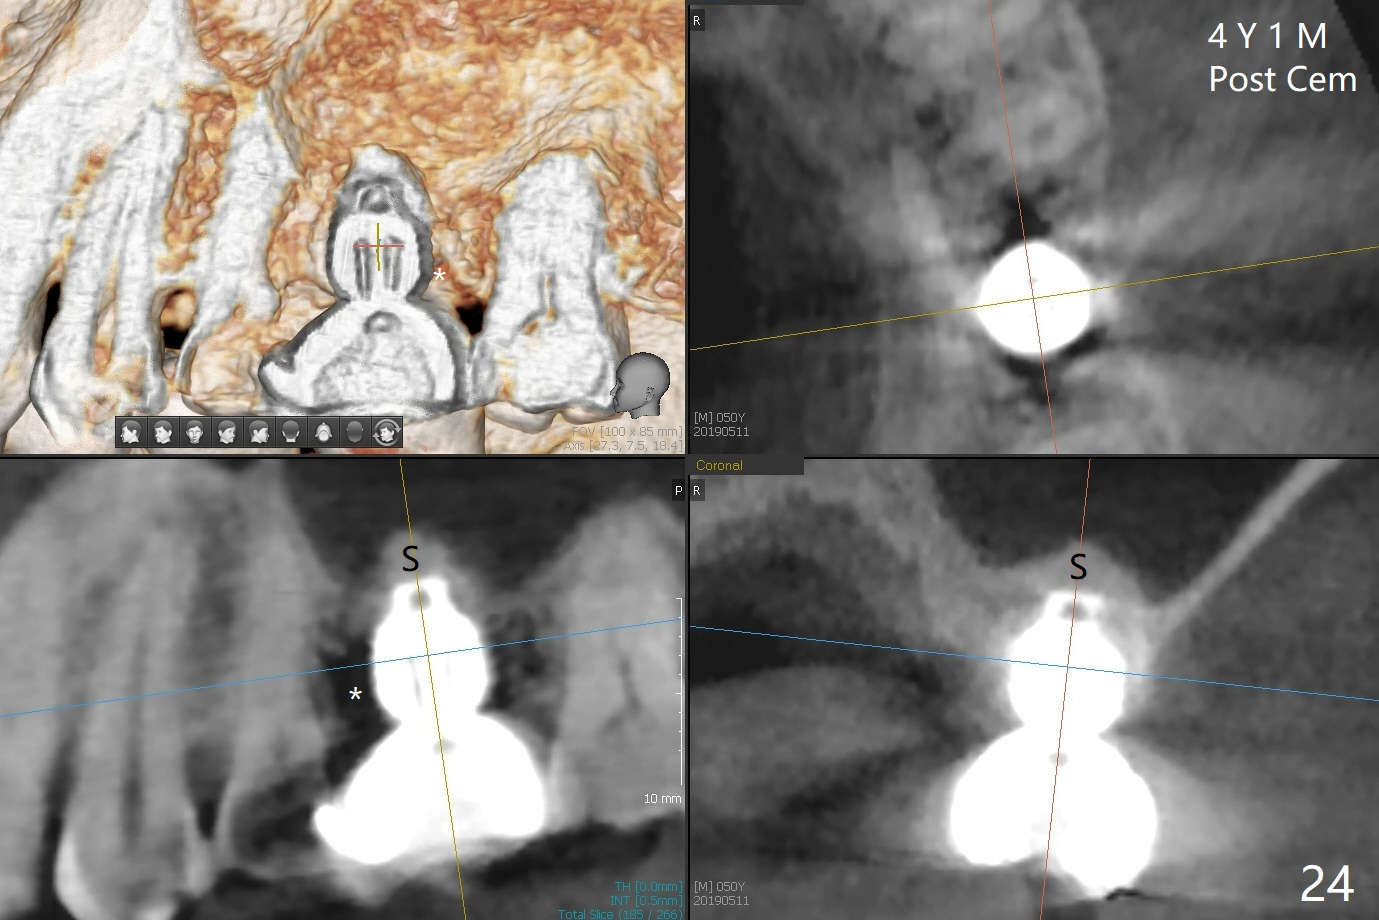

A 45-year-old man has lost the tooth #14 for a while (Fig.1); bone height is 5.4 mm. An extra wide and short implant is planned. Torus palatinus is large, suggesting that bone density should be high. A 6 mm tissue punch is chosen, but it is placed more palatal. If it were placed in the middle of the ridge, there would be no buccal keratinized gingiva (incision may avoid this issue). Additionally, the buccal portion of punch is made incomplete so that there is pedicle on the buccal side when the flap is raised (Fig.4,8: F). It is expected that the excess portion of keratinized tissue will form thick gingiva buccally. Osteotomy proves that bone is dense (Fig.2 (4.5x11 mm tap). Typical sinus lift is finished with placement of 6.4x6 mm (extra wide) bone-level implant (Fig.3, >55 Ncm). Following further torque, Fig.4 shows that the implant (I) is sub-gingival (<). Bitewings are taken to confirm that the implant plateau is at the crestal level (Fig.5,6 ^). PA shows sinus lift (Fig.7 *). The lingual aspect of the implant and healing abutment (H) is further bone grafted and covered by collagen dressing (Fig.8 *). The wound is protected with perio dressing. When the latter dislodges 7 days postop, the collagen dressing and bone graft are lost as well (Fig.10), while the buccal flap remains vital (Fig.9). The lingual exposed plateau should be able to heal normal. The collagen dressing should have been fixed in place by suture or as simple as a dental floss. There is mild nasal hemorrhage 1-2 days postop, possibly related to sinus membrane perforation and inability of Collagen Dressing to cover the perforation and contain the bone graft. When the patient returns for #9 implant placement in 3 weeks postop, the buccal flap reduces in size (Fig.11 *), while the palatal wound has healed with minimal exposure of the implant (Fig.12). Sinus graft remains in place 3 months postop (Fig.13); the buccal flap appears to have incorporated into a part of the gingiva (Fig.14). The bone density of the sinus lift appears to increase 10 days later when an abutment is placed (Fig.15 *). Although oral hygiene is pristine, there is apparent crestal bone resorption 12 months (Fig.16) and 20 months (Fig.17) post cementation, probably due to unfavorable crown/implant ratio and bruxism as well as pre-implantation bone loss (Fig.18,19). In contrast, an immediate implant in the same patient avoids pre- or post-implantation bone loss. In fact both the soft (Fig.20) and hard (Fig.21) tissues remain healthy 2 years 8 months post cementation. The sinus lift remains 3 years 8 months post cementation (Fig.22), while the crestal bone loss persists. The patients keeps complains of food impaction distal associated with bad smell 4 years 1 month post cementation. In fact the distal proximal contact is within normal limit. The bad smell is probably due to crestal bone loss (Fig.23 (pan), 24 (CT) *) and periimplantitis. Bone graft, PRF and Cytoplast membrane will be needed and fixed in place with long healing screw. When the patient returns for crown redo, he also reveals floss related gingival hemorrhage. There is pain associated with palatal sulcus probing with light gingiva erythema. Review of CT coronal section shows possible palatal (Fig.25 P) bone loss (*).